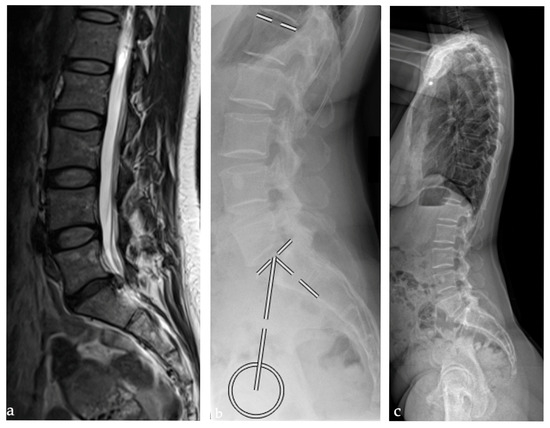

2.2. Radiographic Analysis